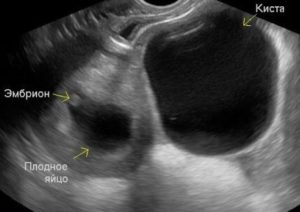

Снимок УЗИ. Одновременное наличие кисты, плодного яйца и эмбриона. Нажмите для увеличения

Болезненность в животе в первые недели беременности наблюдаются из-за воспаления органов мочеполового тракта. На усмотрение врача лечение проводится амбулаторно или стационарно.